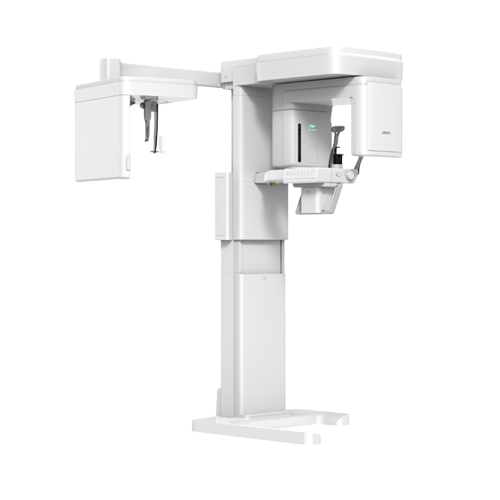

원내 기공ㆍ디지털 치과

진료 시스템

원내 기공과 디지털 분석 시스템을 바탕으로

원내 기공과 디지털 분석 시스템을 바탕으로

CT·CAD/CAM·3D 스캔 기반의 정밀 시스템으로

치과의사와 기공사가 만드는 1:1 맞춤 보철 - READ MORE

- Digital Optimum

- 진단부터 진료까지,

디지털 시스템 구축 - 오차를 줄인 정밀하고 완성도 높은 진단과 치료가 가능합니다